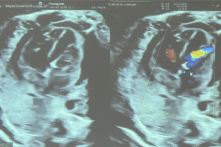

Thêm một ca thông tim can thiệp xuyên tử cung cứu bào thai

7 ngày sau ca thông tim can thiệp bào thai đầu tiên thành công tại Việt Nam, thêm một bào thai 29 tuần tuổi được thông van tim thành công trong bụng mẹ.